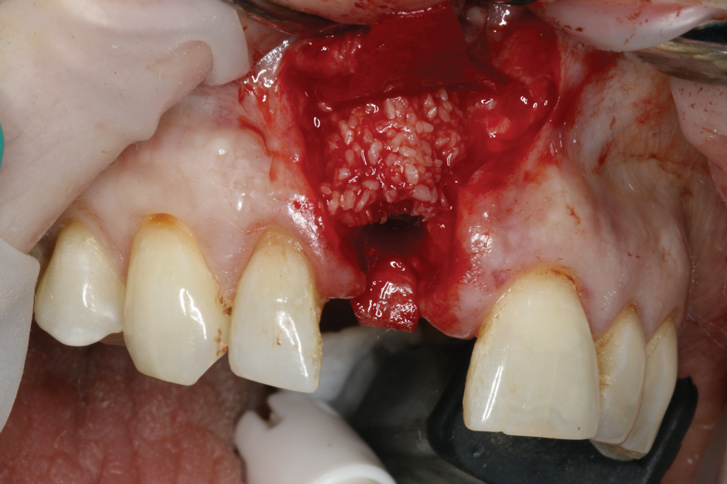

8. Tooth No. 8 with diagnosis of Grade III socket, requiring extraction followed by guided bone regeneration and a rotated pedicle flap to gain hard and soft tissue for future implant placement.

Figure 8

9. Tooth No. 8 with diagnosis of Grade III socket, requiring extraction followed by guided bone regeneration and a rotated pedicle flap to gain hard and soft tissue for future implant placement.

Figure 9

10. Tooth No. 8 with diagnosis of Grade III socket, requiring extraction followed by guided bone regeneration and a rotated pedicle flap to gain hard and soft tissue for future implant placement.

Figure 10

11. Tooth No. 8 with diagnosis of Grade III socket, requiring extraction followed by guided bone regeneration and a rotated pedicle flap to gain hard and soft tissue for future implant placement.

Figure 11

Based on the single extraction socket roadmap developed by El Chaar and colleagues, the socket of tooth No. 8 was diagnosed as Grade III and would require initial treatment that included the extraction of failing tooth No. 8 followed by simultaneous guided bone regeneration and soft-tissue augmentation by means of a rotated palatal pedicle flap (Figure 8 through Figure 11).27,28 The principles of and guidelines for both the ridge augmentation and rotated pedicle flap have been described in the literature and will not be focused on in this case report.27-30 The patient was temporized with a bonded Maryland bridge that was adjusted to avoid creating pressure on the tissue during healing (Figure 12).